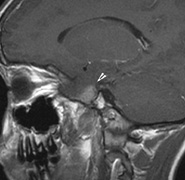

OPTIC NERVE GLIOMAS

Optic pathway gliomas arise from the astrocytes of the optic nerve. Most are pilocytic astrocytomas and typically remain intradural, extending in the subdural space. Malignant transformation is rare. There appear to be two growth patterns62:

- Perineural growth pattern, correlating with a diagnosis of NF1. The tumor expands in the subarachnoid

space and the optic nerve is compressed as a central ribbon. On

T2-weighted MRI, this may be seen as a low-intensity core with surrounding

high-intensity rim. Increased tortuosity of the optic nerve is also

associated with this growth pattern (Fig. 5).63

- Intraneural growth pattern, correlating with the absence of NF1.

The incidence of optic pathway gliomas in NF1 is difficult to estimate, as the majority are asymptomatic and do not affect vision. In NF1, radiographic evidence of an optic nerve glioma occurs in 15% of patients.64,65 Most tumors are neither suspected historically nor detected by ophthalmic examination.65 Even when optic nerve gliomas become clinically detectable, visual function often remains stable in the absence of any intervention.66,67 Thus routine computed tomography (CT) imaging, even in patients with a known optic nerve glioma, is controversial. The potential risks of repeated radiation exposure in a child with a tumor-suppressor gene defect is a consideration. MRI studies are more revealing than CT but may require sedation or anesthetic and are costly. An MRI is often recommended at the time of diagnosis, but in most cases routine “follow-up” MRIs are unnecessary. Annual ophthalmic clinical examination for relative afferent pupillary defect (RAPD), visual acuity, visual fields, color vision, and funduscopy is usually all that is required, as no therapeutic action is likely to be taken unless there is significant and progressive visual involvement.

Optic nerve gliomas may involve the optic chiasm and be associated with endocrine disorders or nystagmus.68–70 Surgical excision of chiasmal gliomas (Fig. 6) carries a high risk of visual loss. Invasion of the hypothalamus or the third ventricle carries a poor prognosis, with greater than 50% 15-year mortality rate.71 One review of radiation treatment for chiasmal gliomas collated data from small case series and found no significant long-term improvement in visual function, progression, or mortality with radiation treatment.71 Other reports suggest that radiation doses over 4500cGy improve symptoms and slow progression of chiasmal gliomas over several years.72 Adequate tumor coverage by radiotherapy results in irradiation of normal brain and nearly all children need hormone replacement.73 Chemotherapy is an alternative.74,75

|

- Optic glioma (Fig. 5)